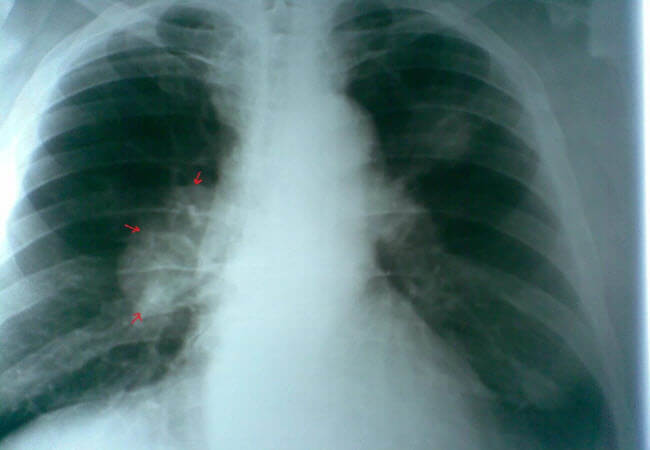

Медики попереджають, що від раку легенів щорічно вмирають тисячі некурців. У зв’язку з чим критично важливо розпізнати перші ознаки захворювання, що дозволить зробити ранню діагностику і швидше почати лікування. До ключових симптомів хвороби відносяться: кашель, який не проходить через дві або три тижні, стійкі інфекції грудної клітки, постійна задишка, хронічна втома, втрата апетиту і незрозуміле скидання ваги, кашель з кров’ю, біль при диханні, посилення давнього кашлю. Існують і інші, менш поширені ознаки, такі як зміна зовнішнього вигляду пальців, наприклад, коли вони стають більш вигнутими або їх кінчики збільшуються. Набряк обличчя і шиї, дискомфортні відчуття плечах і хрипкий голос також в цьому списку.